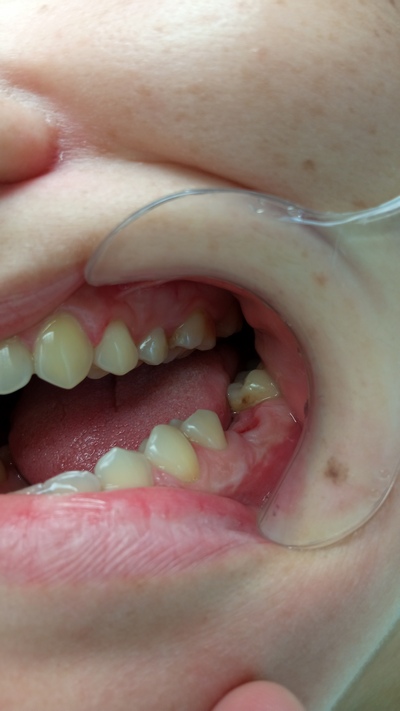

- Осмотр и изучение 3Д снимков показал хорошее состояние полости рта, отсутствие кариозных полостей и каких либо воспалительных процессов.

- В ходе осмотра состояние полости рта было хорошее, зубы рядом с отсутствующим были сохранены и не поражены кариесом.